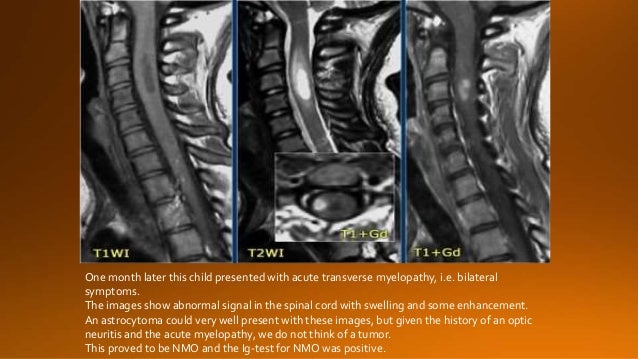

Your message goes here